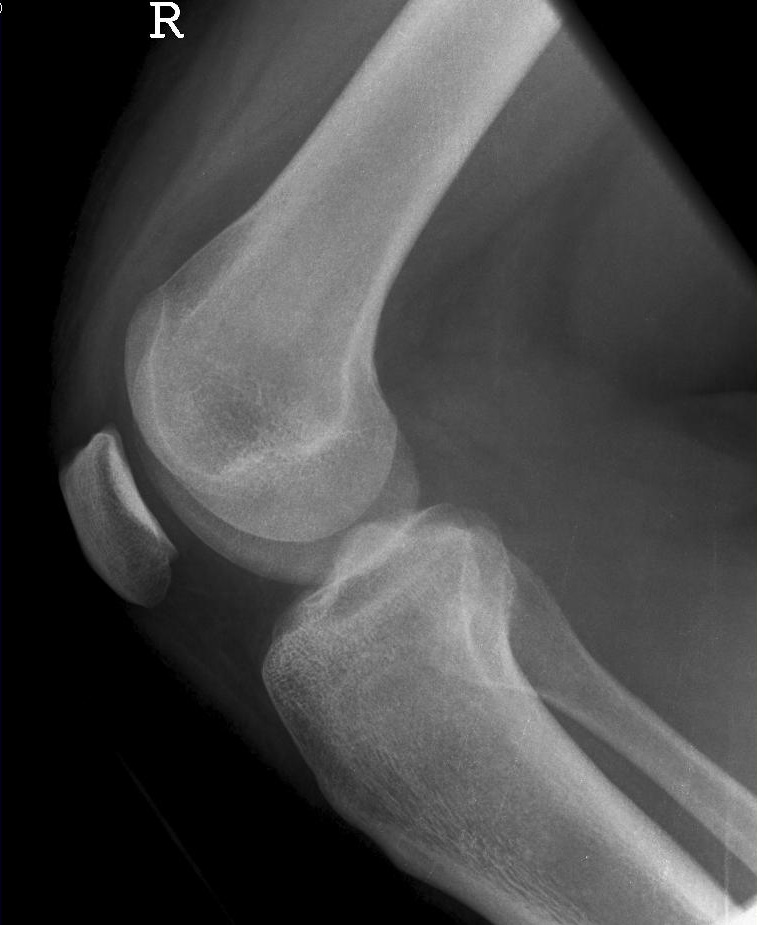

Knie seitlich

126_5.jpg

Fehler

Die filmferne Femurrolle "rutscht" mit ihrer Konturlinie nach unten und überdeckt die ganze Eminetia intercondylaris. Das Knie ist seitlich getroffen, jedoch war der Unterschenkel nicht auf einer Höhe mit dem Oberschenkel.

Abhilfe

Richtige Zentrierung, streng seitlich, aber auch präzise Lagerung des Knies und des ganzen Beines, wobei die Ferse mit einem Keilkissen angehoben wird (nicht zu viel und nicht zu wenig).